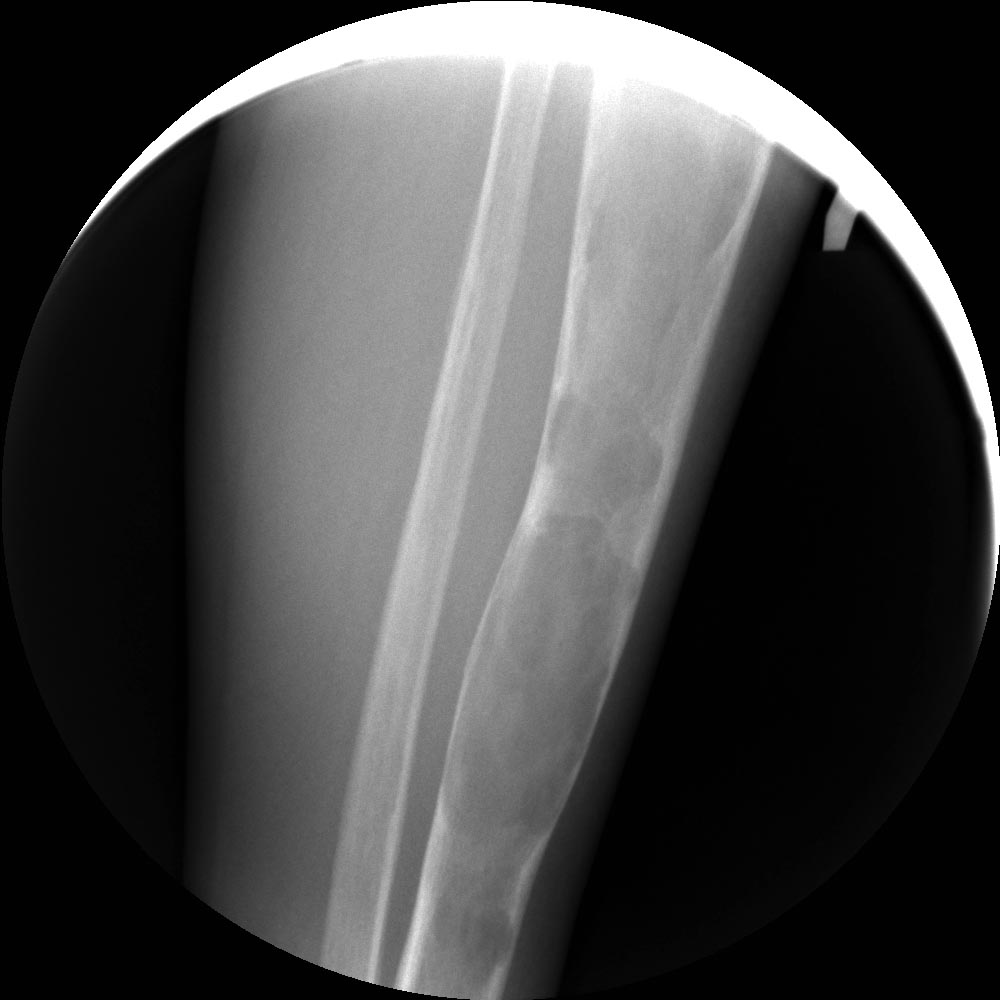

Фиброзная дисплазия бедренной, большеберцовой, малоберцовой костей

слева.Заключение:Фиброзная дисплазия бедренной, большеберцовой,

малоберцовой костей слева.15.10.2014 15:01 Рентгенография левого

15.10.2014 15:01 Рентгенография левого коленного сустава в одной

проекцииФиброзная дисплазия бедренной, большеберцовой, малоберцовой

костей слева.Заключение:Фиброзная дисплазия бедренной, большеберцовой,

малоберцовой костей слева.